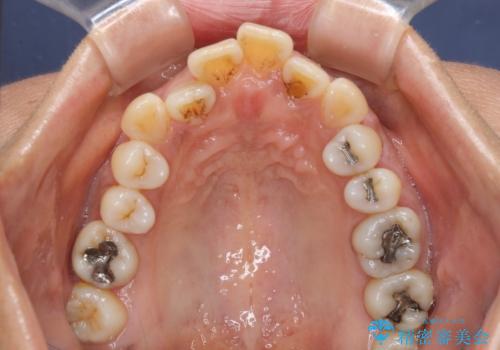

- 八重歯やクロスバイトを気にして来院された患者様です。

口元の突出感はありませんでしたが、デコボコが強く、非抜歯矯正とすると出っ歯仕上がりとなる可能性があったため、上下左右の第一小臼歯4本を抜歯し、ワイヤー装置にて矯正治療を行うこととしました。